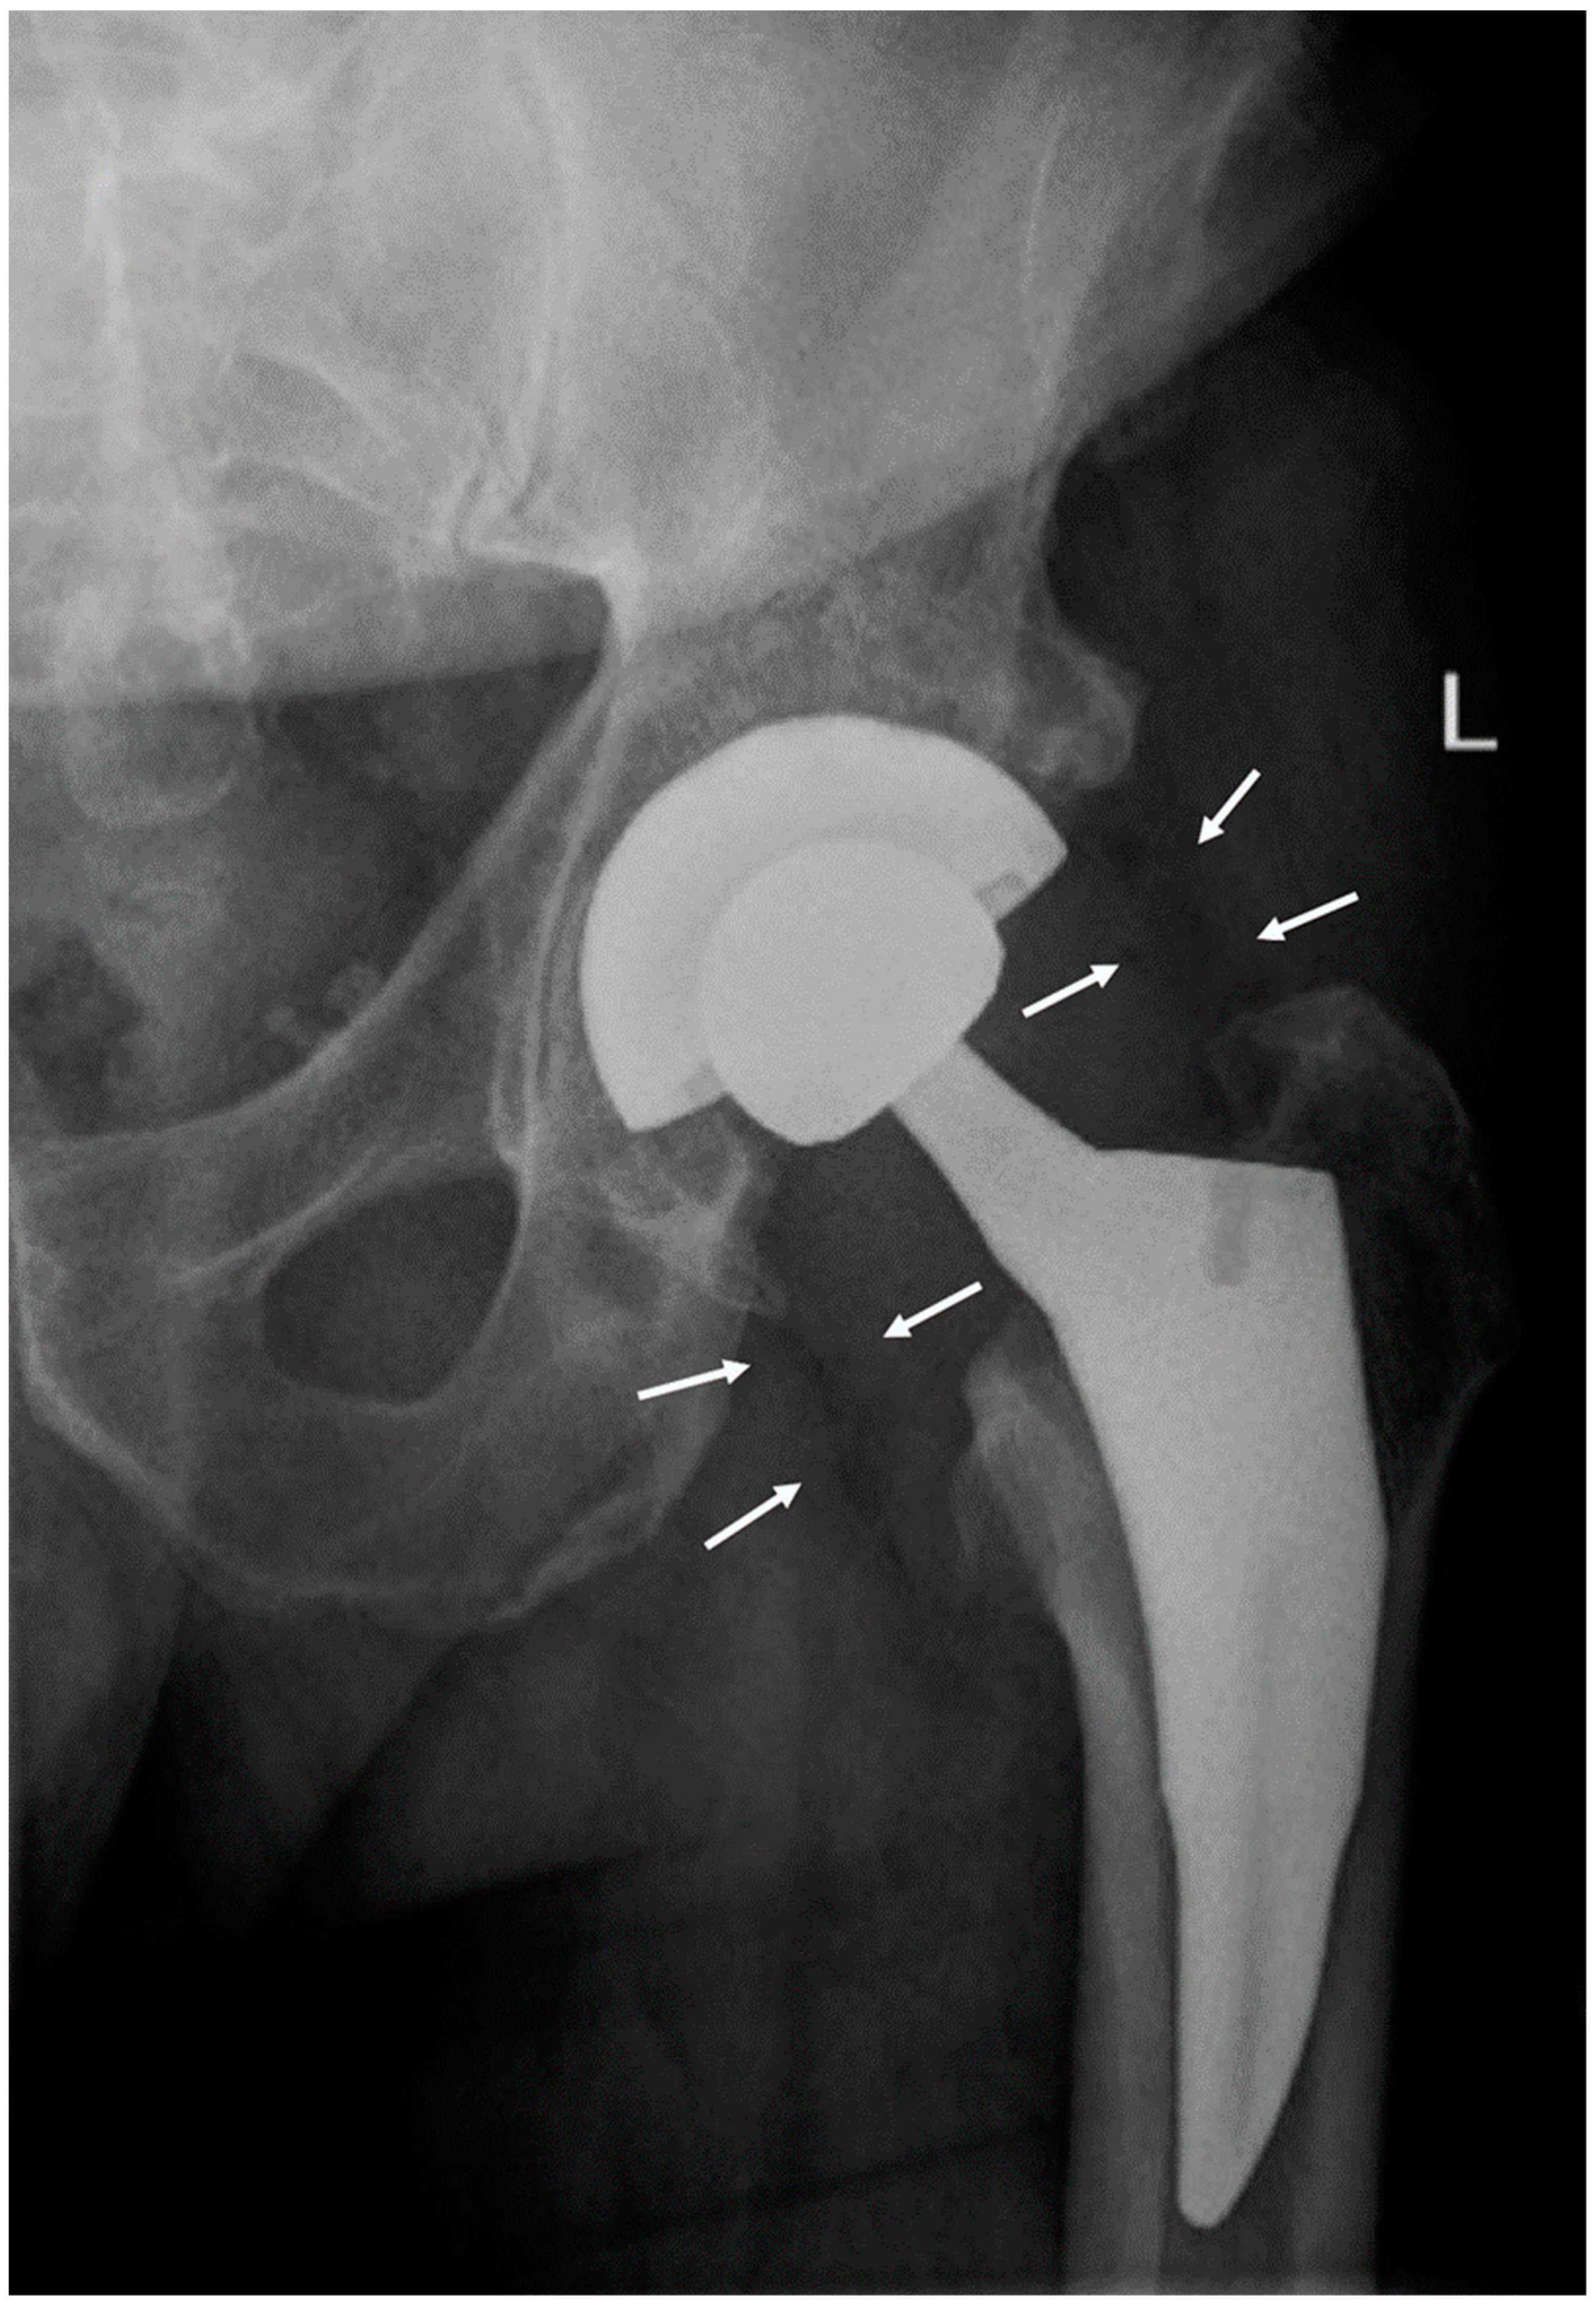

A radiograph of the hip showed periprosthetic gas in soft tissue (Figure 1). A CT scan of the neck and soft tissues along with an MRI of the C-spine were negative for compression or deep space abscess. Left shoulder arthrocentesis was negative for crystals with unremarkable chemistry. The blood pressure differential between arms prompted a CT angiogram of chest, abdomen, and pelvis that was negative for large vessel vasculitis.

Figure 1. A hip radiograph demonstrating periprosthetic gas in soft tissue. Two foci of gas are outlined by white arrows; the largest focus of gas is at the lateral aspect of the hip. The patient underwent a total left hip replacement eight days prior to the onset of tetanus symptoms and demonstrated no other evidence of deep or superficial injury.